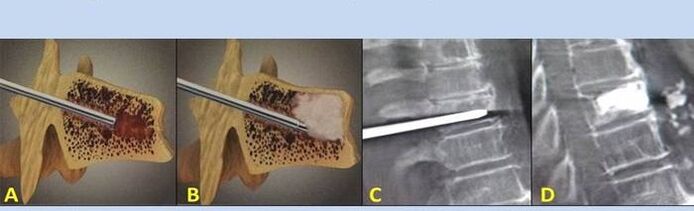

- nucleoplasty– Remove the disc core.This surgery relieves pressure on the nerve endings.

- puncture vertebroplasty– Methods of stabilizing the vertebrae.During the surgery, doctors fill the cavities in the spine with bone cement.